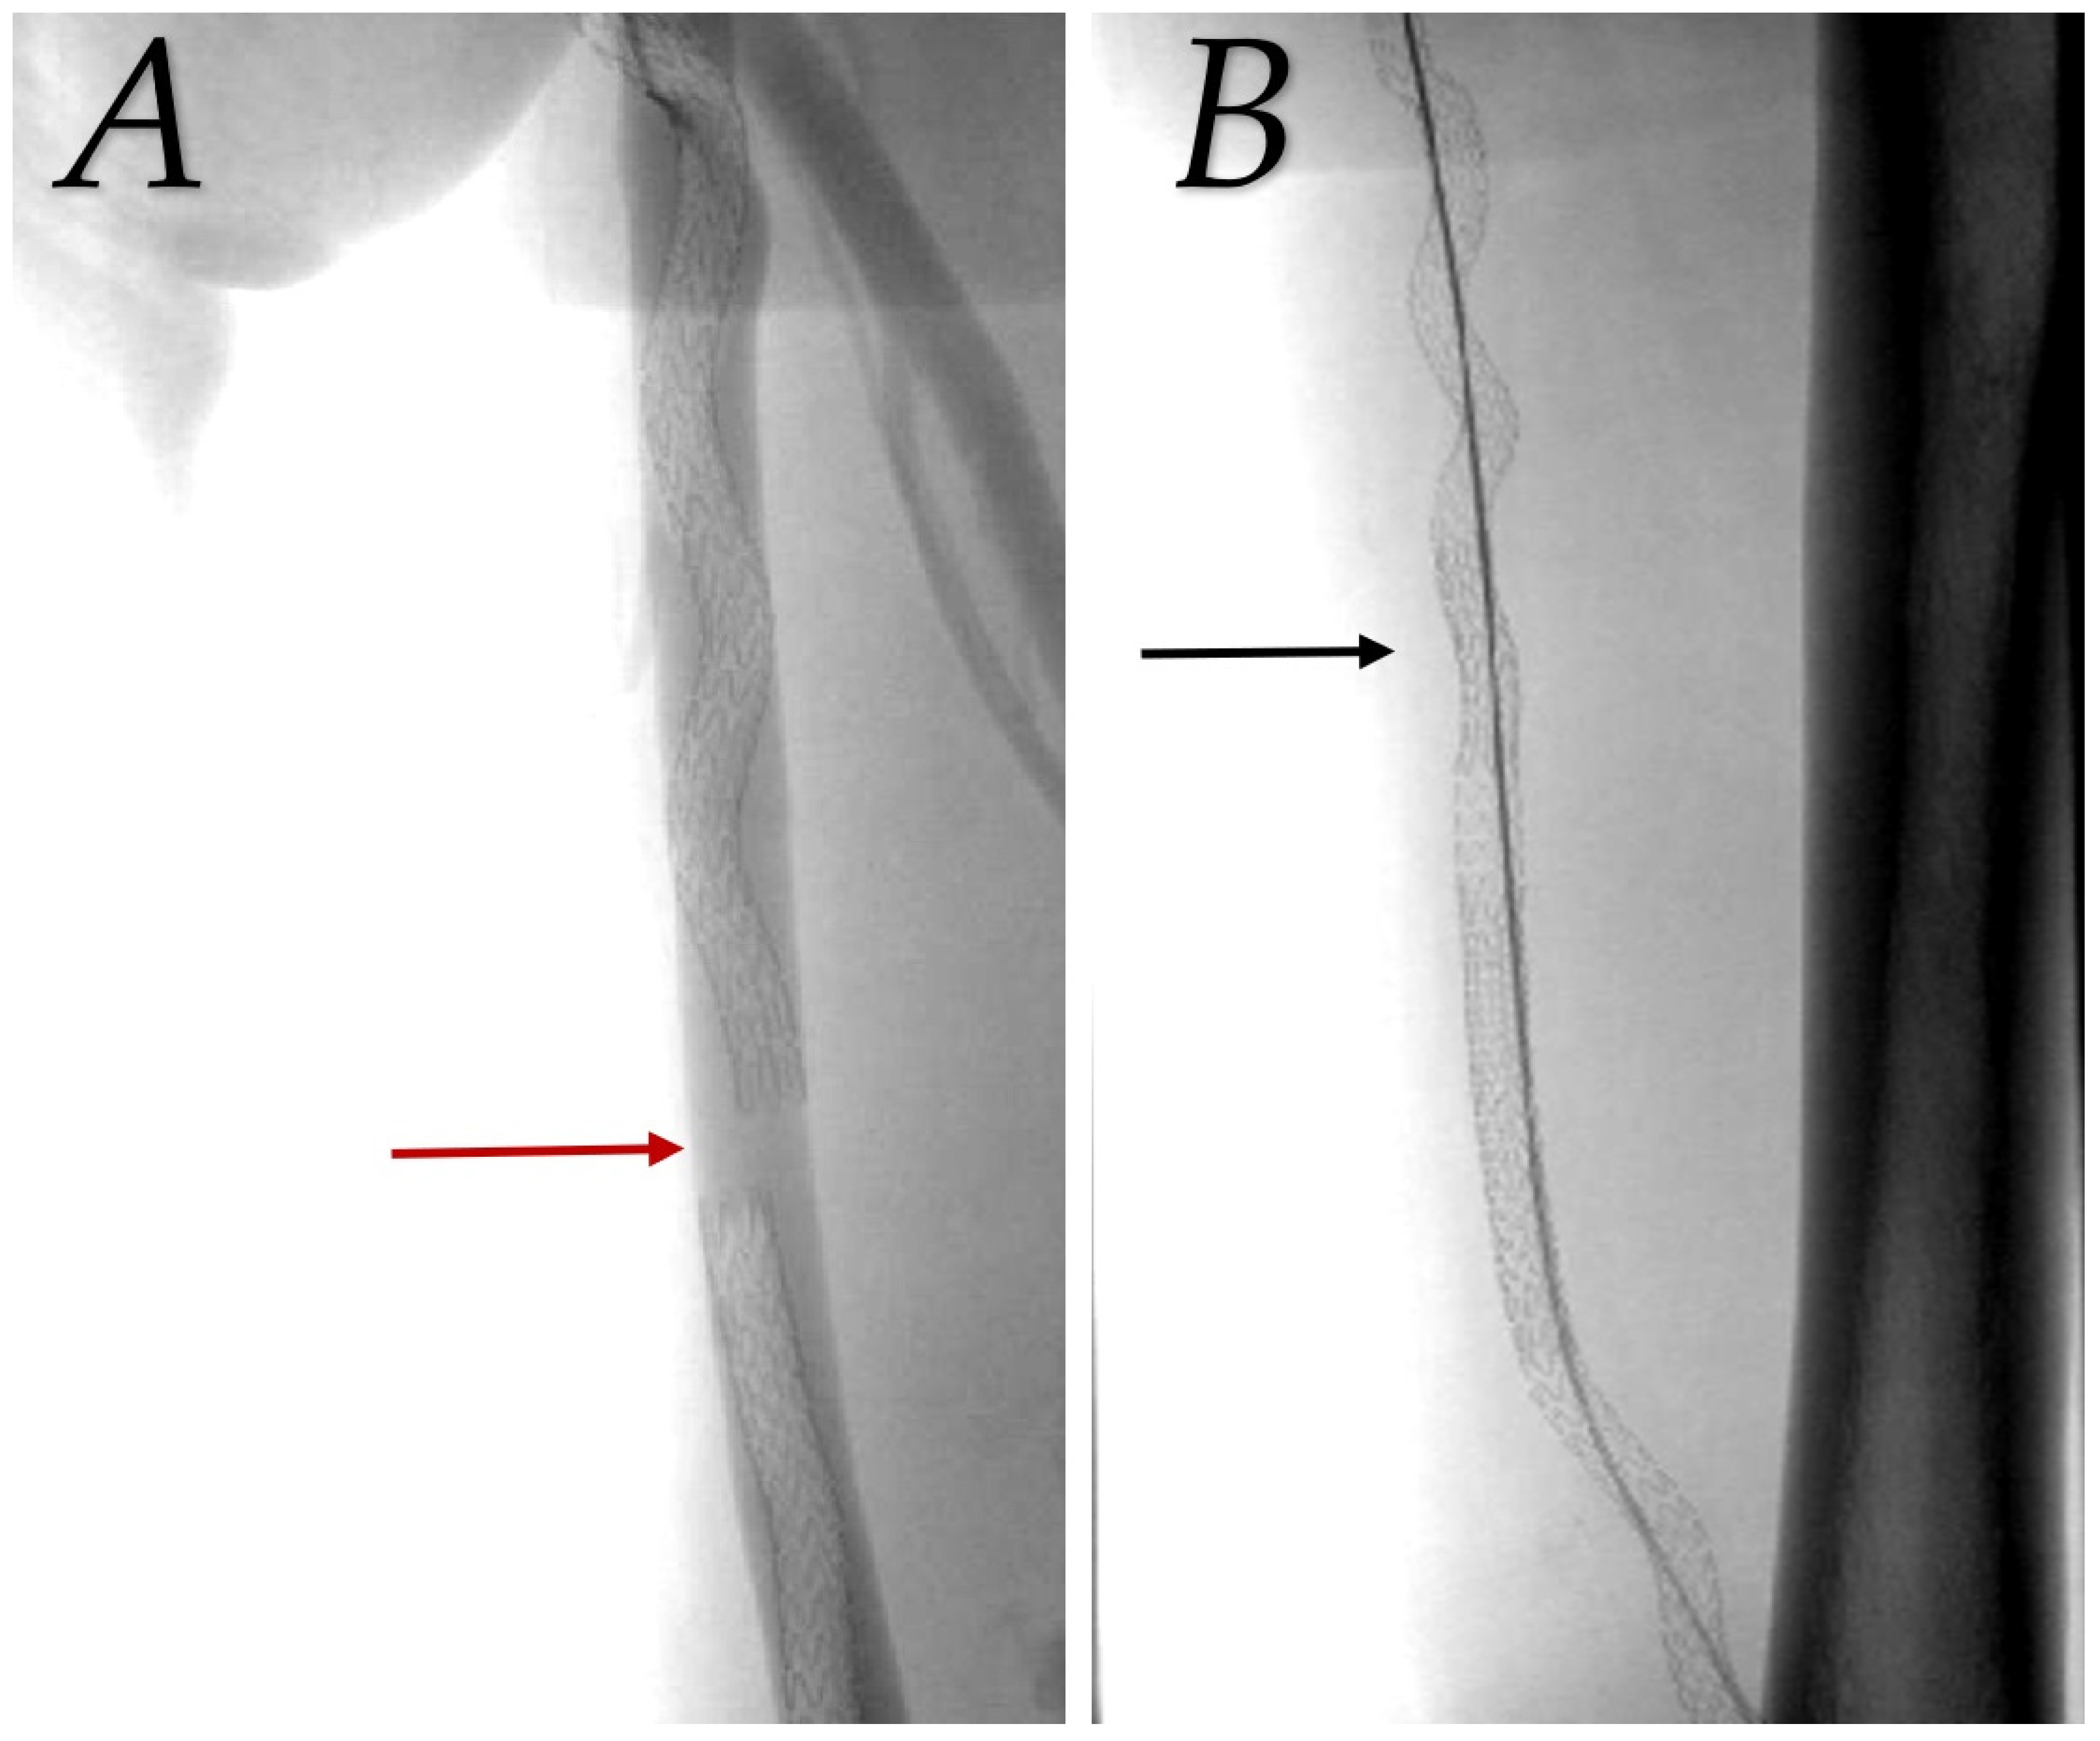

During the first year, five angioplasties were performed for endovascular transvenous bypasses, three for prosthetic grafts, and one for venous bypasses. We had two cases of stent-graft migration due to an insufficient overlap in the endovascular group, which required a salvage procedure to bridge migrated graft components one day and one month after primary procedure (see Figure 3). Primary-assisted patency was 88.9% for transvenous endovascular, 75.9% for prosthetic grafts, and 93.2% for venous bypasses after 12 months (p = 0.013 for prosthetic versus venous bypass). To maintain graft patency, six additional angioplasties were performed during year two in the endovascular group, two in the prosthetic graft, and none in the vein group. At the 24-month visit, both endovascular (79.2%, p = 0.002) and venous bypasses (86.4%, p < 0.001) were significantly more patent than prosthetic grafts (48.1%) with regard to primary-assisted patency. This was even more pronounced at 36 months (see Figure 4).

Figure 3.

Salvage procedure to bridge detached stent grafts. (A) Red arrow indicates a gap between migrated covered stents in femoral vein. (B) Additional stent graft (black arrow) used to bridge detached segment and treat iatrogenic arteriovenous fistula.